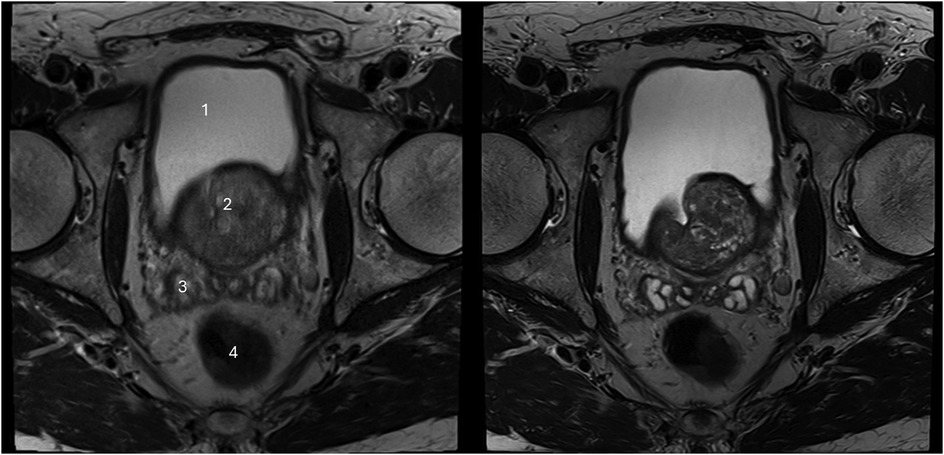

The sharpness of the prostate was evaluated to be significantly superior in T2HR compared to T2S, with medians of 5 (4–5) vs. 4 (4–4) (p < 0.001). The contours of the lesion were also rated superior, with a median of 5 (4 -5) in T2HR vs. a median of 4 (4–4) (p < 0.001). The delineation of the prostate border was also rated to be improved in T2HR [median of 5 (4–5)] as compared to T2S [median of 4 (4–5); p < 0.001]. However, the extent of the motion artifacts was evaluated to be worse in T2HR compared to T2S, with medians of 5 (4–5) vs. 5 (5–5) (p = 0.009). Please see Table 3 for the full details. Figures 2–4 show examples of both sequences.

Figure 4. Imaging of a 71-year-old man with suspicion of prostate cancer. T2S on the left-hand side and deep learning-reconstructed T2HR on the right-hand side. The seminal vesicles are much sharper and have improved contrast in T2HR. No suspicious lesion was found by either reader (PI-RADS 2). (1) bladder; (2) transition zone of the prostate; (3) seminal vesicles; (4) rectum.